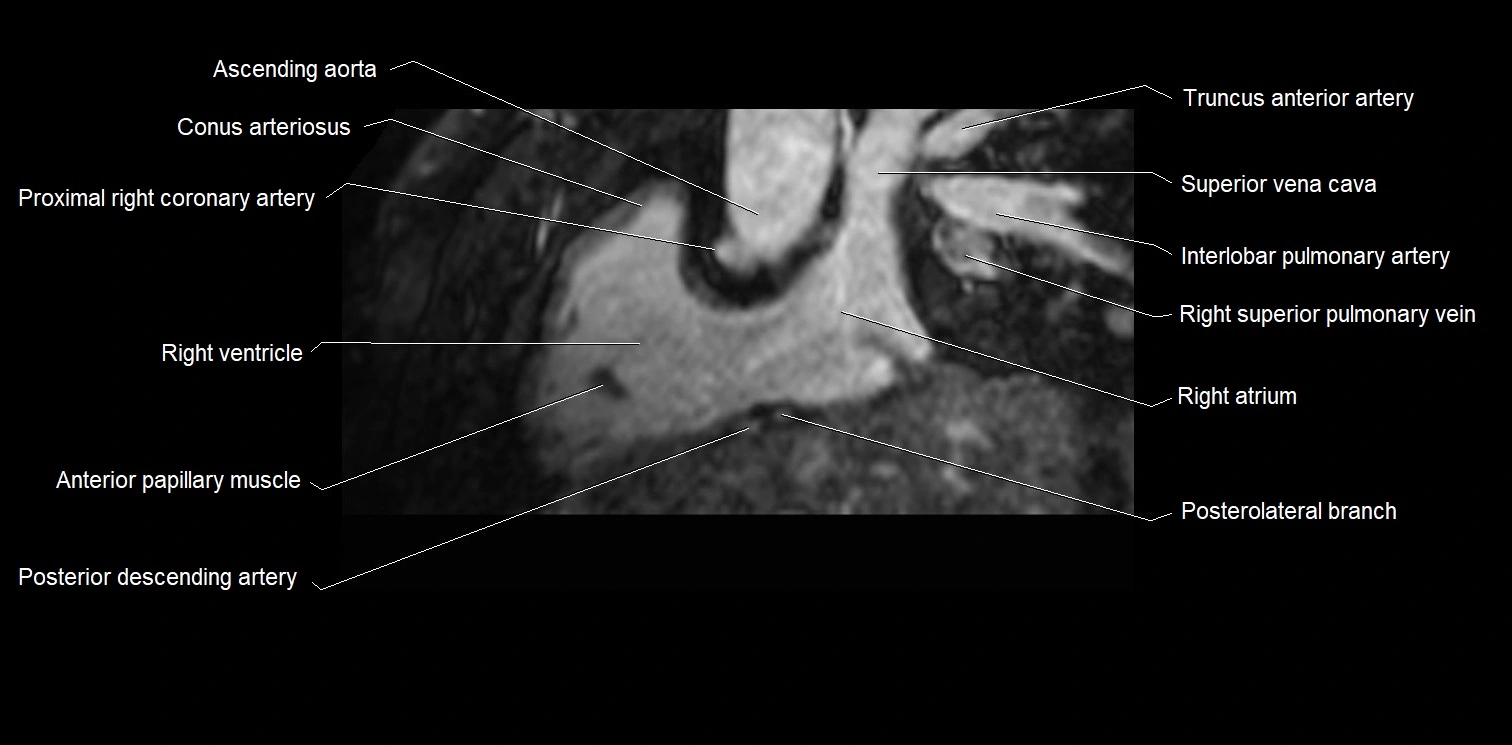

MRI image